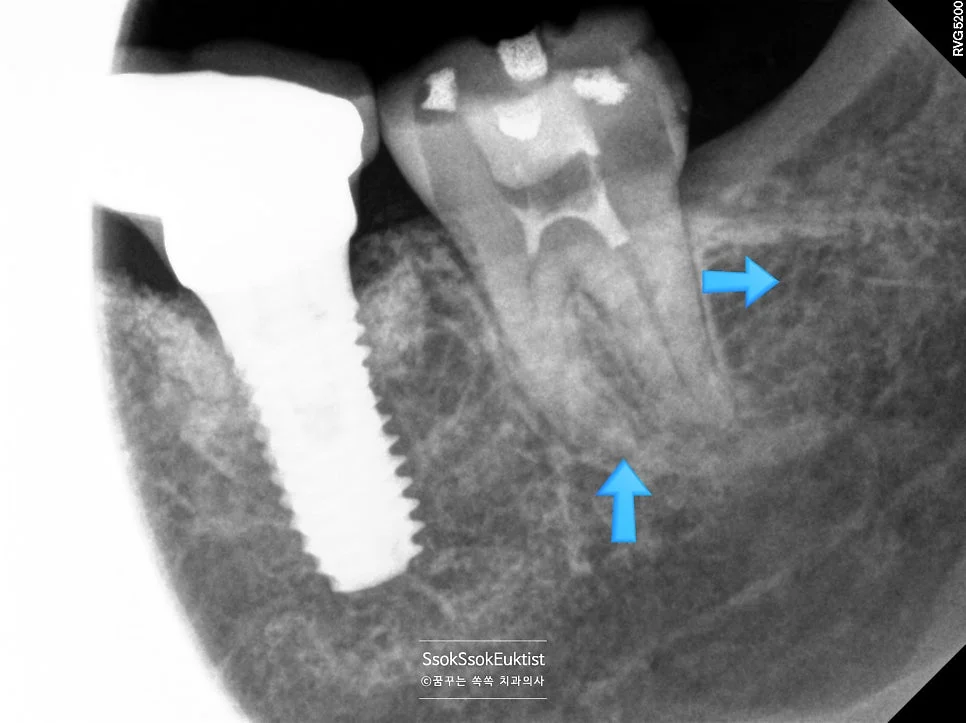

제2대구치 신경치료 완료 방사선

신경치료 완료 방사선 — 신경관이 가득 채워진 모습 (화살표: 레진으로 채워진 충치 부위)

치아의 신경관이 가득 채워진 것 같으면 잘 된 신경치료입니다^^ 한편, 크게 있던 충치도 예쁘게 레진으로 채워졌네요(사진상에서 화살표로 표시된 하얀 부분).

보통 신경치료의 경우 서울쏙쏙치과에서는 2번 정도에 마무리가 되지만, 이 치아의 경우 3번의 내원에 치료가 마무리되었습니다.

임플란트 앞 치아 인레이 치료

한편, 임플란트 바로 앞 치아의 충치도 함께 인레이 치료를 시행합니다.

임플란트 인접 충치 인레이 치료

임플란트 인접 치아 충치 — 인레이 치료 진행